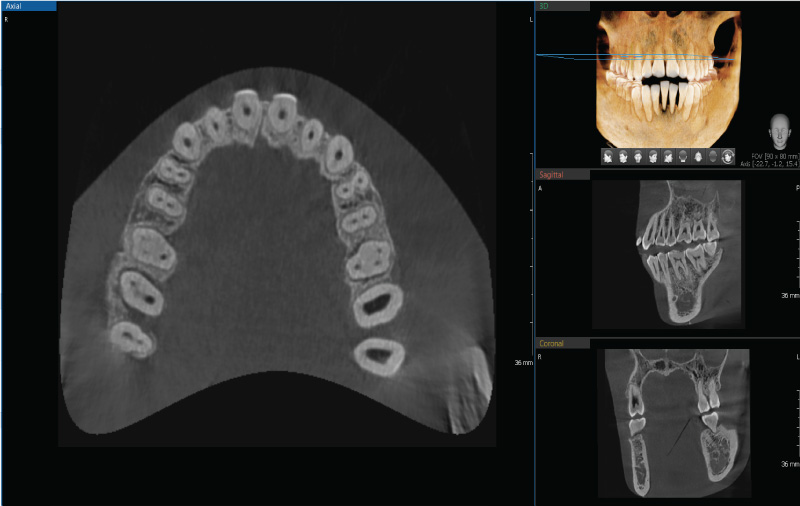

Анатомическая зона сканирования 10х8 см

Зона сканирования 10х8 см предоставляет необходимую диагностику при планировании лечения зубов верхней и нижней челюсти

Размер поля обзора при КТ (см)

10x8 (Анатомический)

Размер вокселя

0.2 мм / 0.3 мм